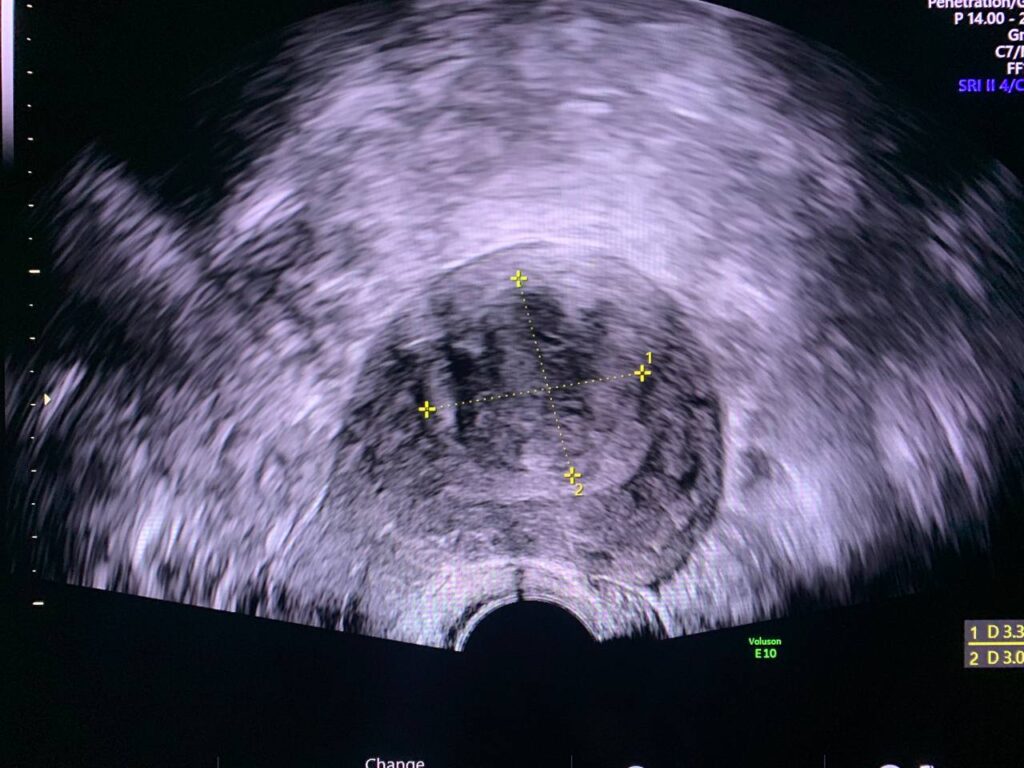

Bulky size, A/V uterus, endometrial lining thickness 3.6mm, displaced by submucosal intramural hyper vascular hypoechoic solid mass size about 33x31mm, could be fibroid ? , focal adenomyosis? , for further study to exclude other pathology.